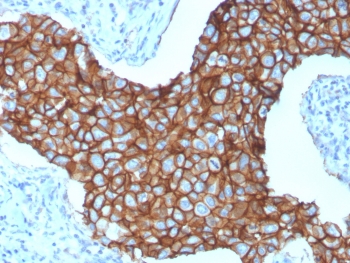

IHC staining of FFPE human breast cancer with HER-2 antibody (clone ERBB2/3257). HIER: boil tissue sections in pH6, 10mM citrate buffer, for 10-20 min and allow to cool before testing.

Recognizes a protein of 185kDa, which is identified as c-erbB-2/HER-2/neu. Its epitope is localized in the extracellular domain. C-erbB-2/HER-2 is a member of the EGFR family. This MAb is specific and shows minimal cross-reaction with other members of the EGFR-family. Receptors of this family are located on the plasma membrane and consist of an extracellular ligand-binding domain that is connected to a large intracellular domain by a single transmembrane sequence. c-erbB-2/HER-2 protein is over-expressed in a variety of carcinomas especially those of breast and ovary.